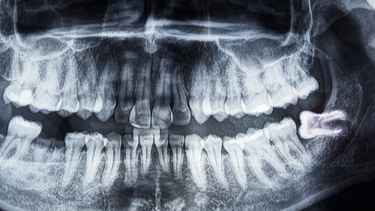

Răng số 8 hay còn được gọi là răng khôn là chiếc răng mọc cuối cùng ở mỗi cung hàm. Thời điểm răng xuất hiện thường vào độ tuổi trưởng thành từ khoảng mười bảy đến hai mươi lăm tuổi. Khi xương hàm đã phát triển hoàn chỉnh và không còn nhiều không gian, răng số 8 dễ bị kẹt trong nướu hoặc xương. Điều này dẫn tới tình trạng răng mọc lệch, mọc ngầm, xoay sai hướng hoặc cắm sâu sát thần kinh.

Nhổ răng số 8 vì vậy thường phức tạp hơn so với răng khác. Nếu chân răng chạm sát ống thần kinh hàm dưới hoặc xoang hàm trên thì trong và sau phẫu thuật dễ xảy ra những biến chứng sau khi nhổ răng số 8. Tuổi của người nhổ càng lớn, vị trí mọc càng sâu, phẫu thuật càng khó và tỉ lệ rủi ro càng tăng.

Do đó trước khi nhổ bác sĩ thường yêu cầu chụp phim để đánh giá rõ tình trạng răng và đưa ra phương án phù hợp. Chuẩn bị tốt ngay từ đầu sẽ góp phần giảm nguy cơ biến chứng.

Có cần chụp phim trước khi nhổ răng số 8 không

Cần thiết vì phim giúp bác sĩ đánh giá chính xác vị trí và hình dạng răng từ đó lựa chọn cách phẫu thuật an toàn.